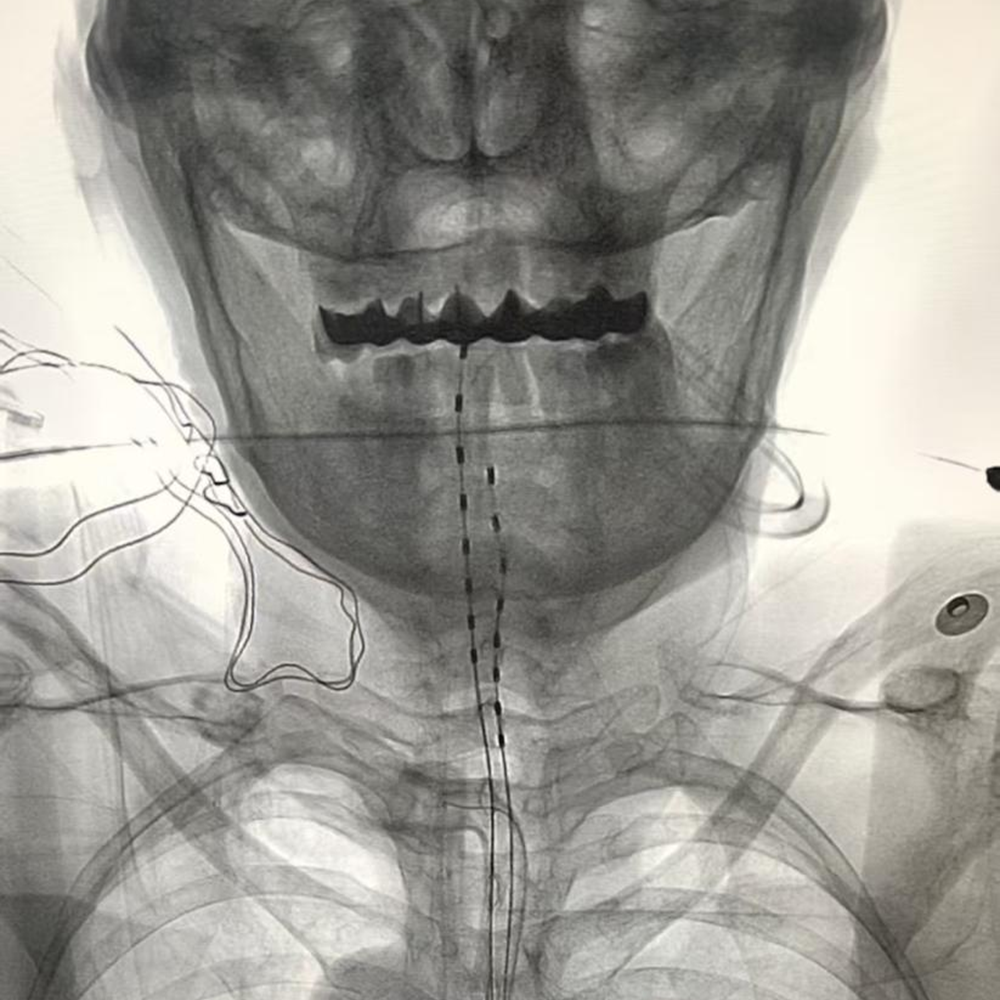

手术在高倍显微镜下完成,无需开颅,仅通过颈部微创切口,将健康一侧的颈7神经精准移位、吻合到瘫痪侧上肢神经,让健侧大脑同时控制双侧肢体,绕开受损的大脑半球,重新建立运动指令通路。

医生在影像引导下,通过毫米级微小切口,将微型电极精准植入脊髓硬膜外间隙,连接皮下脉冲发生器,释放温和电脉冲。